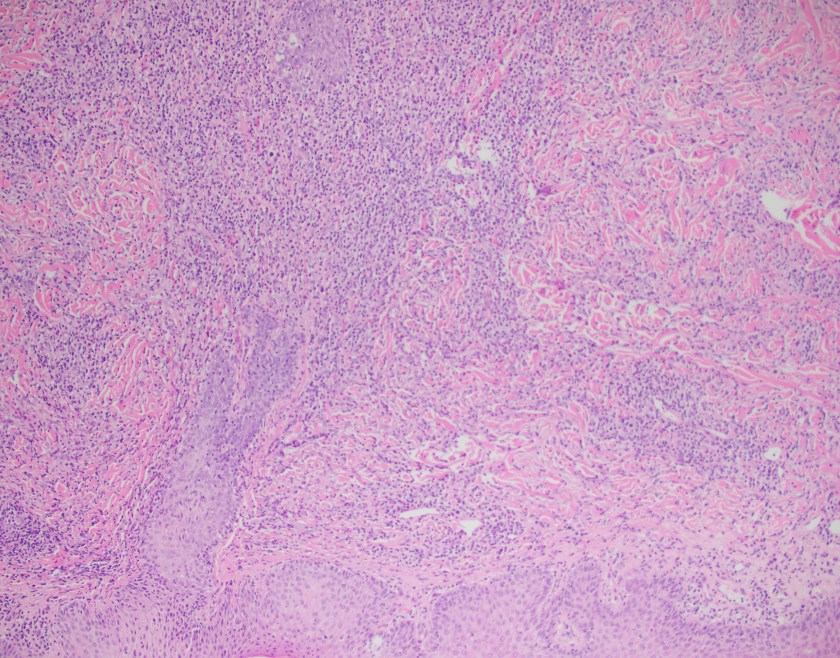

H&E stained sections reveal sheets of large lymphocytes. The lymphoid cells are medium to large in size with irregular nuclear contours and prominent nuclei. Areas of necrosis are prominent. No specific areas of epithelial ulceration are noted. Immunophenotypic characterization of the larger cells reveals positivity for CD20, CD30, CD79a, PAX5, MUM1, Epstein Barr virus encoded RNA (EBER) and a variable Ki-67 proliferation index, which is up to 60-70% in the larger cells, but around 20-30% overall. Only rare cells are positive for BCL-2 and BCL-6. The lymphoma cells are negative for keratin AE1/AE3, CD10, CD4, CD8, CD21, CD23, CD7, CD5, Cyclin D1, CD68, CD56, and CD43. The background T cells express CD5 and CD7 and are a mixture of CD4 and CD8 with CD4 predominance.

We considered the diagnosis of EBV-positive mucocutaneous ulcer (a more indolent entity); however, the lack of history of an ulcer/ulceration and the presence of a mass-lesion (with additional adenopathy) does not support this diagnosis.

The findings are most consistent with EBV-positive DLBCL, NOS (WHO 2017), previously known as EBV positive DLBCL of the elderly (WHO 2008).